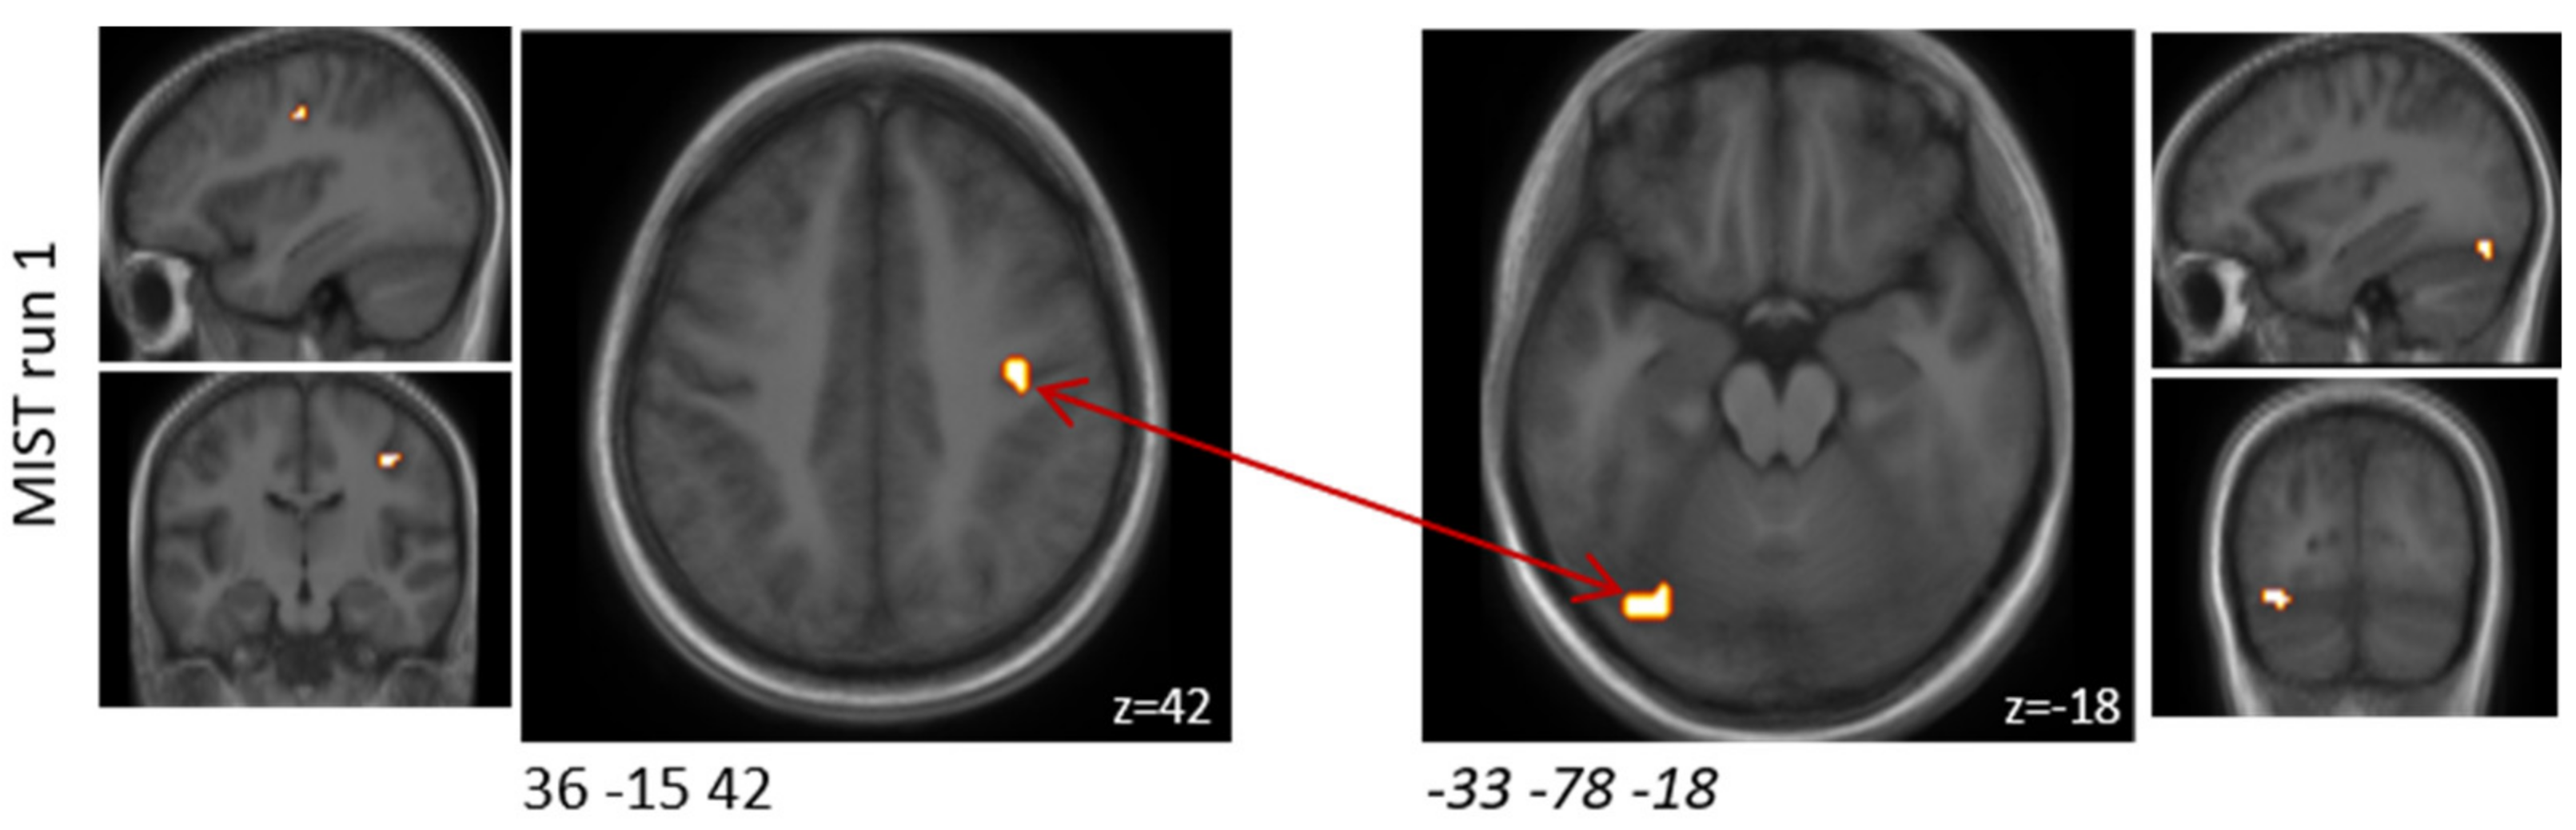

Using cluster-based analysis, activation (probiotics > placebo) (p < 0.1, without correction for multiplicity) was observed in two clusters when comparing the interventions with respect to the differential activity evoked by the challenge paradigm in MIST run one. Those two clusters were located in the rostroventral and dorsolateral areas. In MIST run two and three, no significant differences were found by cluster-based analysis. The results separated by the three MIST runs are reported in Table 2 and Figure 2.

Figure 2. Schematic visualisation of clusters that were found to be associated with changes in brain activity (p < 0.1) when comparing the probiotic and the placebo interventions (probiotic > placebo) and when comparing the experimental and control condition before multiplicity correction during the MIST paradigm. Clusters are superimposed on average anatomical scans. Clusters can be identified by the coordinates of their peak (x y z).

Table 2. Clusters that were found to be associated with changes in brain activity (p < 0.1) between both interventions when comparing the experimental and control condition before multiplicity correction during the MIST paradigm.

MNI Coordinates of Peak (x y z)Cluster Size [mm3]Experimental-Control in Probiotic-Placebo

p-Value *

Experimental-Control in Probiotic-Placebo

Effect Size

Anatomical Region

MIST run 1

−66 −21 2410260.0701.462A40rv, rostroventral area 40 (PFop)

−54 −69 613500.0772.871A37dl, dorsolateral area 37

MIST run 2

none

MIST run 3

* After correction for multiple testing using Bonferroni, none of these alterations passed the level of significance (MIST run 1: p > 0.05/12; MIST run 1: p > 0.05/14; MIST run 3: p > 0.05/3). MIST—Montreal Imaging Stress Task, MNI—Montreal Neurological Institute.